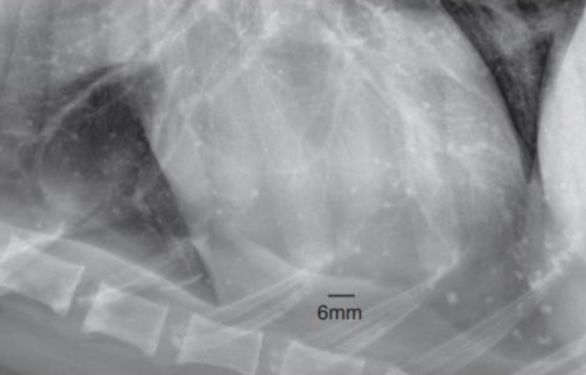

Pulmonary osseus metaplasia : 폐의 석회화 (노령성)![]() (폐전이에 비해 너무 작고, opacity가 bone에 더 가까움) |